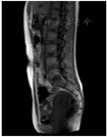

术后病理结果提示低级别子宫内膜间质肉瘤(low-grade endometrial stromal sarcoma, LGESS )(图4)。免疫组化:ER(+++)、PR(+++)、CD10(+++)、VIM(+++)、Caldesmon(+)、DES(+++)、ALK(-)、P53(-)、P16(-)、CyclinD1(灶+)、Ki-67(+,10%)。完善MRI检查显示:子宫大小约7.8 cm×4.9 cm×5.8 cm,宫腔内未见明确异常软组织结节或占位征象,T2WI低信号结合带未见异常增厚,宫颈未见异常,宫旁结构清晰;双侧附件未见异常占位;腹膜后淋巴结未见增大(图5)。考虑到患者年轻、影像学评估无异常、盆腹腔淋巴结未提示转移,告知患者及其家属相关病情及风险后,其选择保留双侧卵巢,于2020年4月7日行TU-LESS全子宫切除术+双侧输卵管切除术+盆腔多点活检术。术中查见:无腹水,行腹腔冲洗液细胞学检查。子宫饱满、质韧,表面光滑,活动好,前次手术的子宫创面未见明显粘连;盆腹腔未见确切肿瘤播散种植。经阴道完整取出子宫,剖视子宫见宫内膜光滑,前次病灶挖除术后创面的剖面未见异常,肌壁未见明显异常。术后病理结果提示:LGESS伴平滑肌分化;手术切缘及腹膜取材活检未见肿瘤累及(图6)。前次手术子宫切口缝合表面取材活检仅提示异物(缝线)肉芽肿(图7)。免疫组化:CD10+++、CyclinD1多灶+、Des++、SMA+、Caldesmon-、ER+++、PR+++、WT1+++、Her2-、P53-、P16-、Ki67(+,25%)。腹腔冲洗液中未查见恶性肿瘤细胞。

注:宫腔内未见明确异常软组织结节或占位征象,盆腹腔淋巴结未见长大